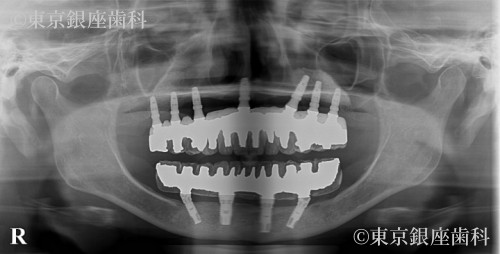

過去のインプラントで十分な結果が得られず再チャレンジし噛む機能を取り戻した60歳代女性の症例

After

以前のインプラントが不十分で再治療を希望。下顎から先にインプラント、上顎洞炎治療後に上顎も実施。難症例ながら最終的に噛める状態を獲得。

上下ワンデイインプラント(再チャレンジ症例)